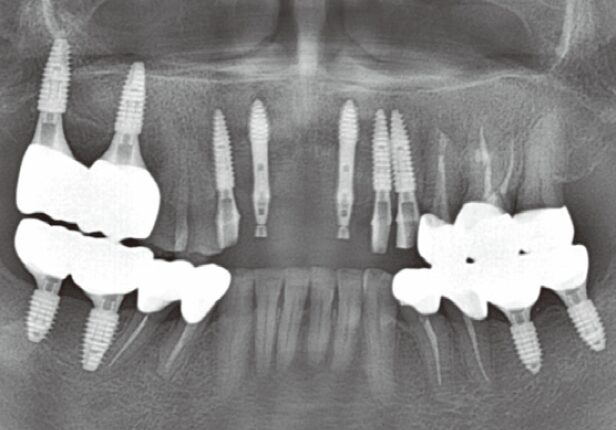

Panorâmica pré-cirúrgica

caso de estudo